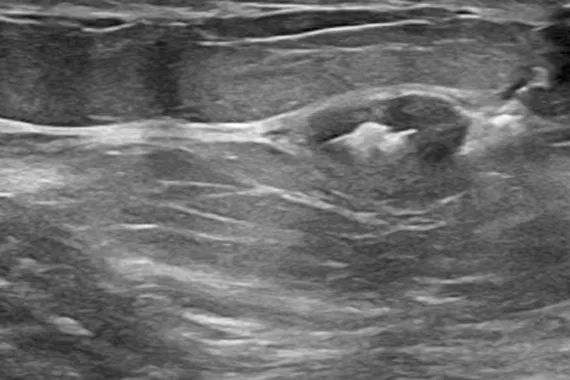

SecurMark® Biopsy Site Markers

Denna markör är utformad för att minimera rörelse,2 har hög synlighet vid ultraljud efter placering och är fortfarande väl synlig 6 veckor efter biopsin, vilket är avgörande vid framtida bröstingrepp.3 Markören består av två delar, en permanent markör och ett biologiskt nedbrytbart nät.

Bildgalleri